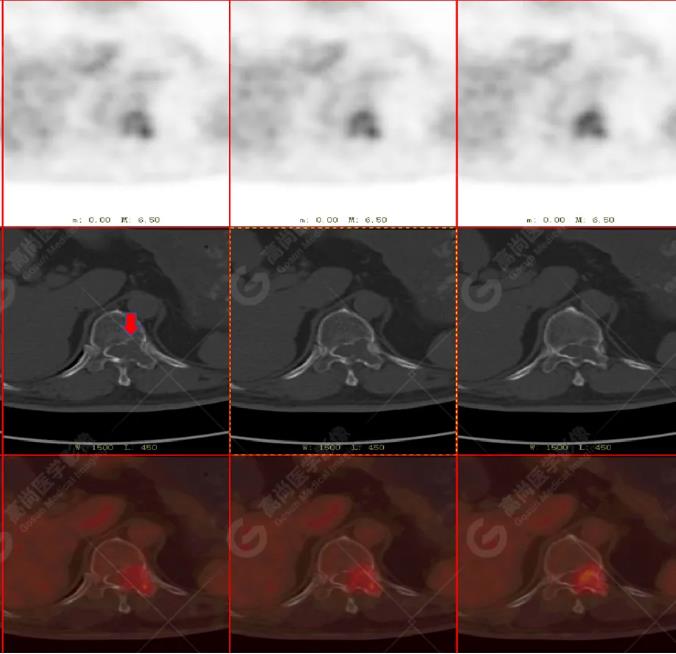

左胸一后肋溶骨性骨質(zhì)破壞,周?chē)檐浗M織形成,F(xiàn)DG代謝增高,SUVmax為10.9。

找到引起骨痛病灶,病因:原發(fā)?轉(zhuǎn)移?感染?

宮頸一片狀稍低密度影,F(xiàn)DG結(jié)節(jié)樣代謝增高,SUVmax為10.2。

最終診斷:宮頸癌伴肋骨單發(fā)骨轉(zhuǎn)移。